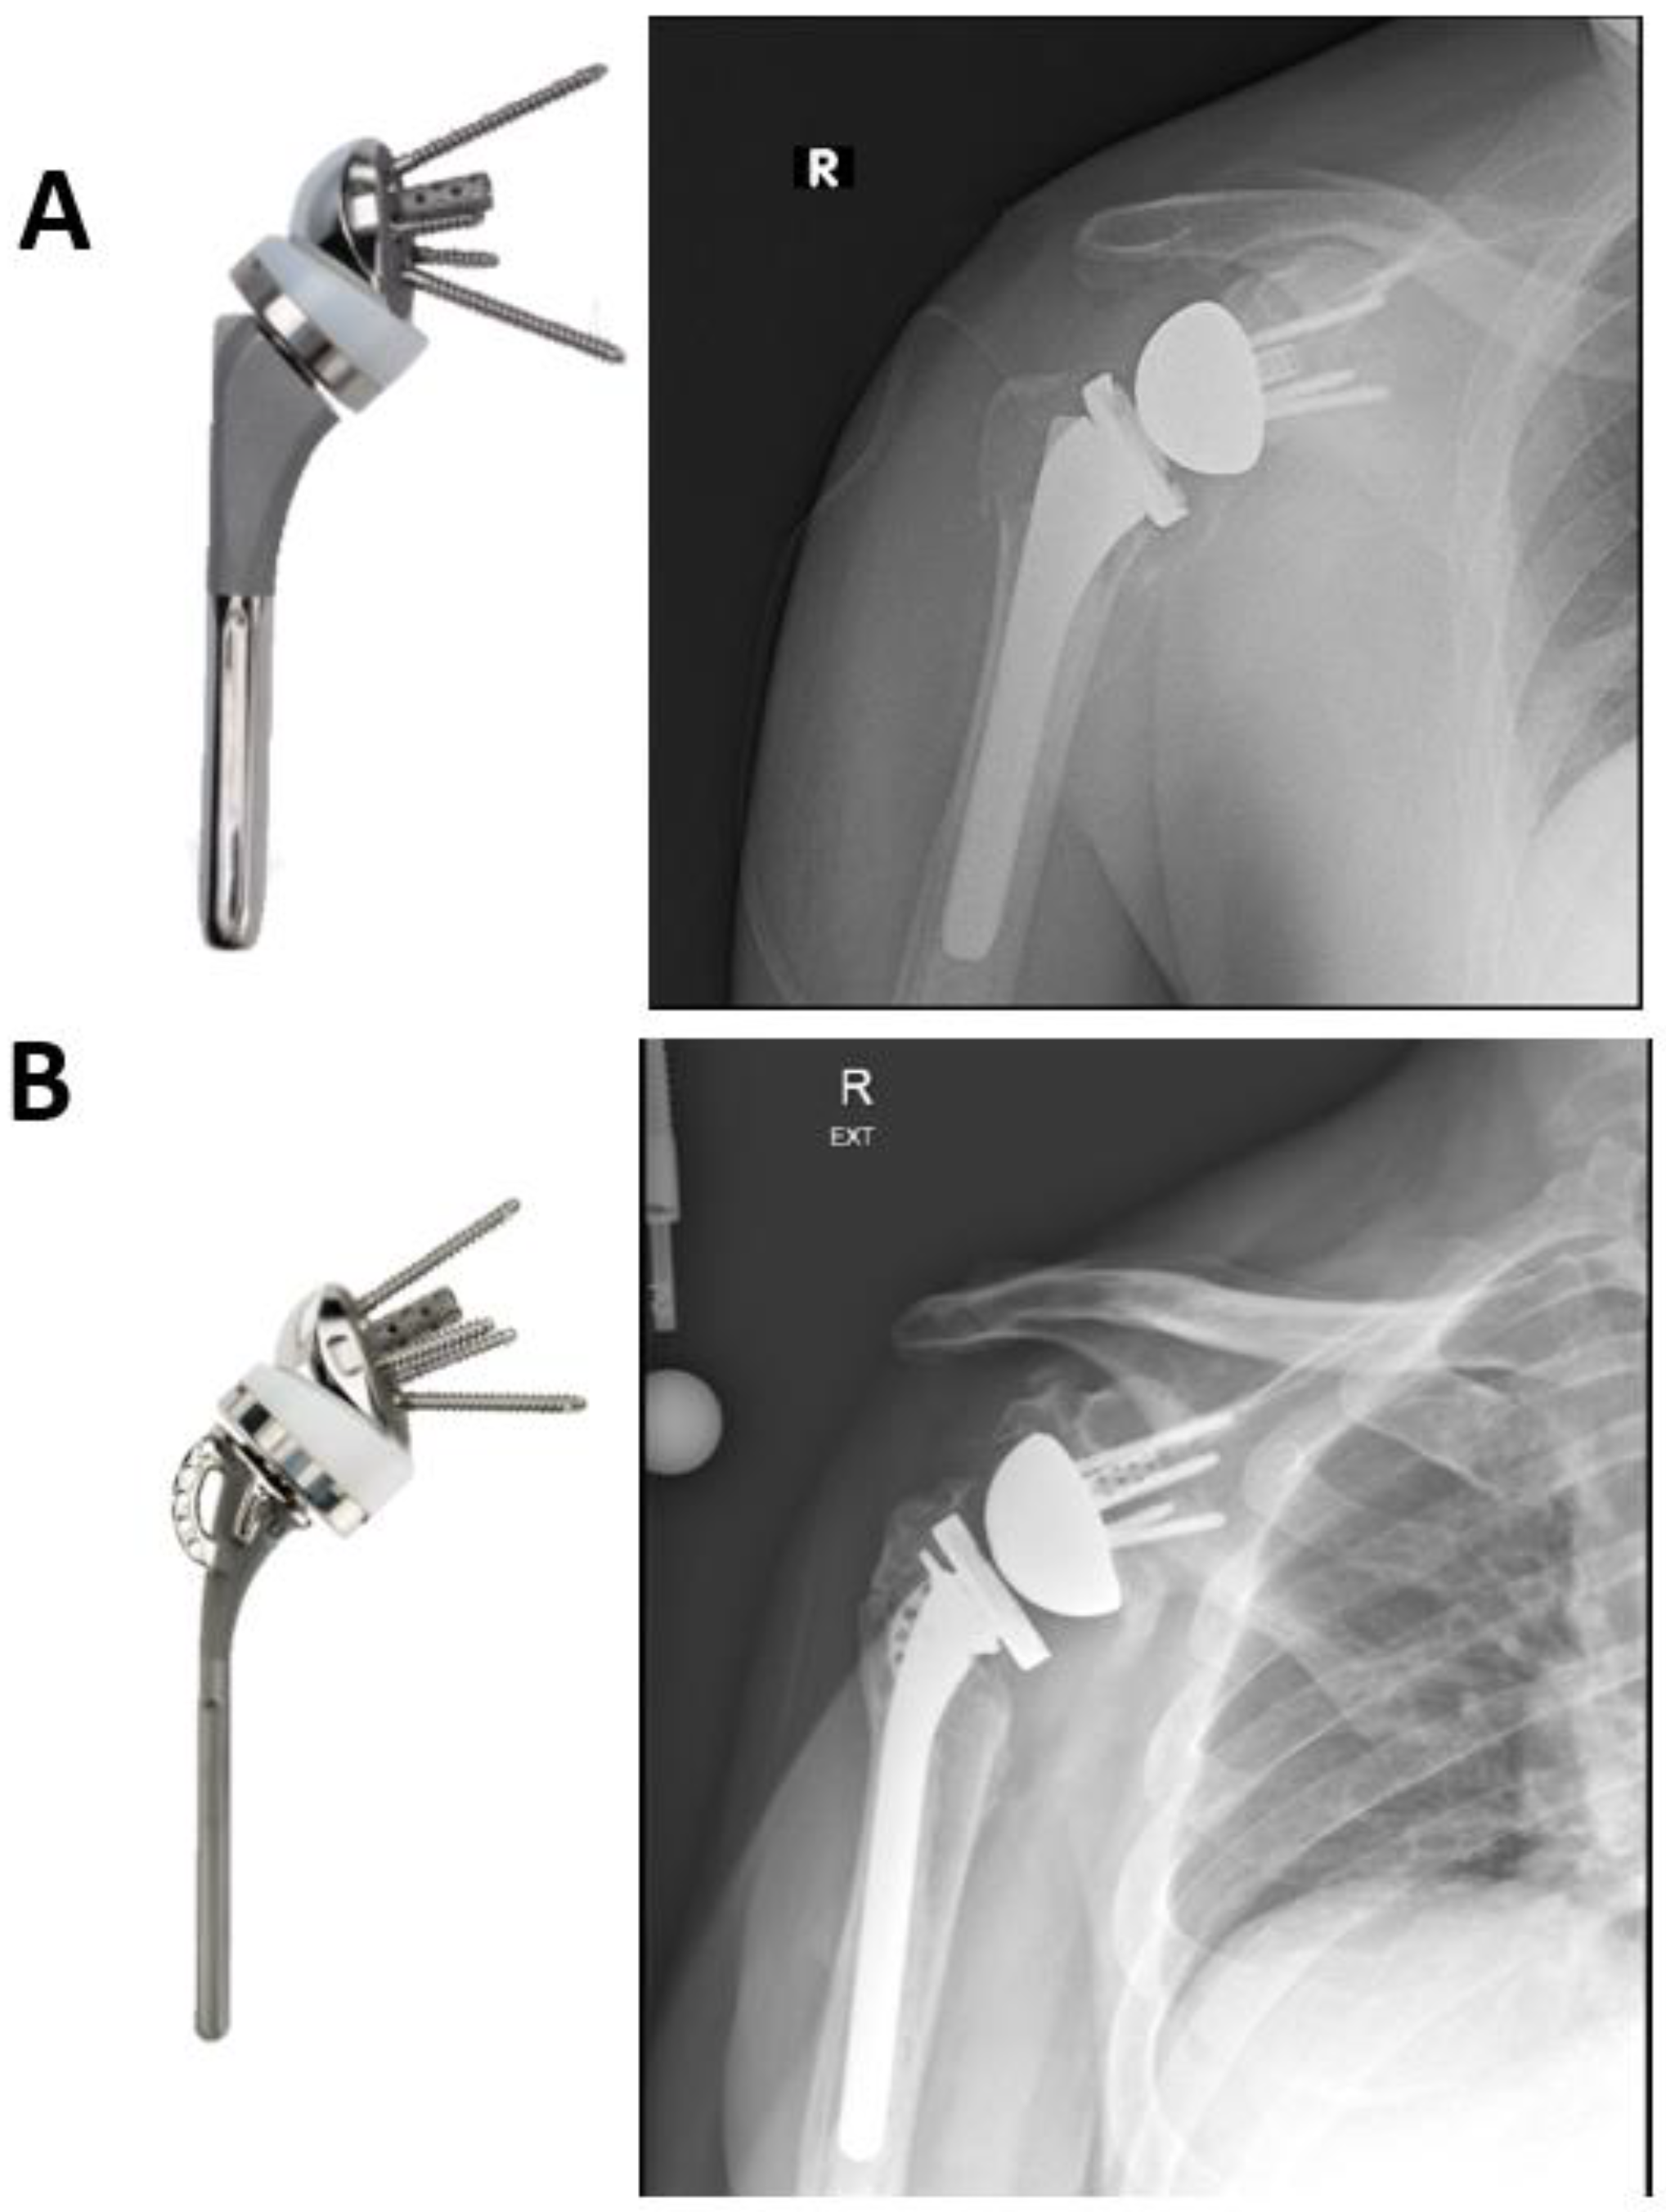

7.2. Standard Humeral Stem versus Fracture Stem